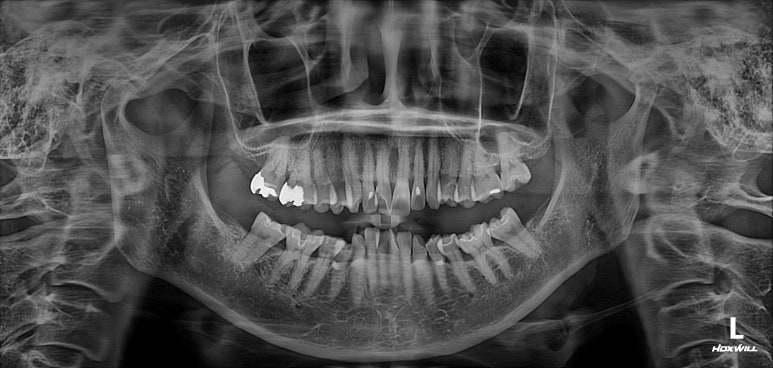

엑스레이를 찍는 이유는 잇몸이 건강한지를 확인하기 위함입니다.

50대 여성분임에도 불구하고 충분히 건강한 잇몸상태를 확인할 수 있었습니다.

그러면.. 교정치료가 가능하다는 뜻입니다.

치아의 뿌리 상태를 확인하기 위한 방사선 사진 촬영 필수!

교정을 하기 전에 무조건 위아래 앞니의 뿌리길이를 체크해야 합니다.

아무래도.. 성인교정의 대부분은 삐뚤어진 앞니 배열의 개선이지요?

그러면 앞니의 움직임이 다소 많을 것이기 때문에, 교정하기에 적합한 뿌리 길이를 갖고 있는지 확인해야합니다.

그런 면에서 이번 환자분은 당연히 합격!